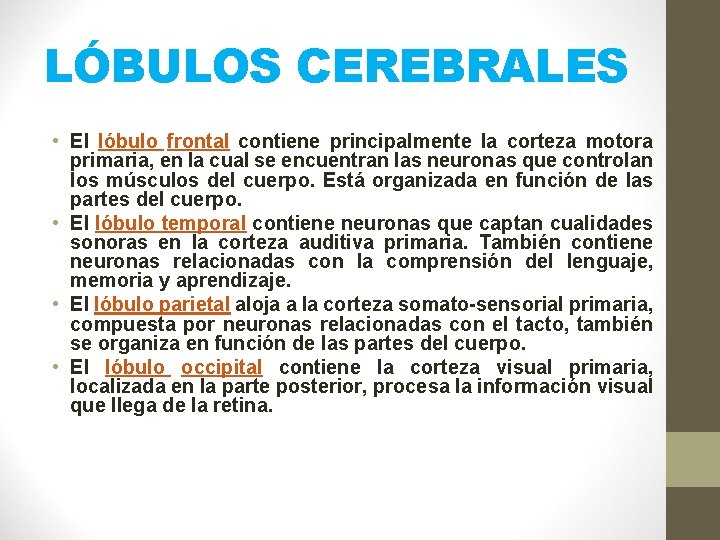

LÓBULOS CEREBRALES • El lóbulo frontal contiene principalmente la corteza motora primaria, en la cual se encuentran las neuronas que controlan los músculos del cuerpo. Está organizada en función de las partes del cuerpo. • El lóbulo temporal contiene neuronas que captan cualidades sonoras en la corteza auditiva primaria. También contiene neuronas relacionadas con la comprensión del lenguaje, memoria y aprendizaje. • El lóbulo parietal aloja a la corteza somato-sensorial primaria, compuesta por neuronas relacionadas con el tacto, también se organiza en función de las partes del cuerpo. • El lóbulo occipital contiene la corteza visual primaria, localizada en la parte posterior, procesa la información visual que llega de la retina.